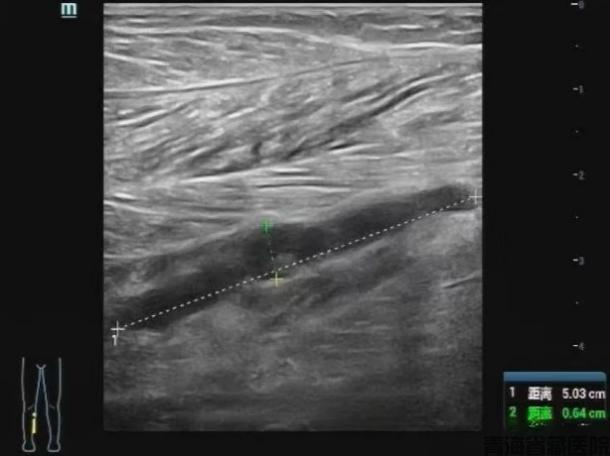

2)超声检查(准确率98%)表现:血管鼓胀变形呈"腊肠样"血流信号突然"消失"探头按压血管无法完全压扁

图片3.png

常规二维灰阶超声检查

小腿肌间静脉管腔扩张,充满低回声,探头加压无法压扁,提示血栓形成